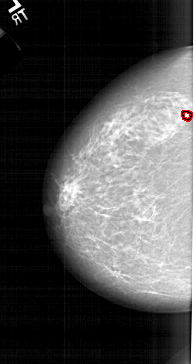

A_1214_1.RIGHT_CC

RIGHT_CC LINES 5341 PIXELS_PER_LINE 3121 BITS_PER_PIXEL 12 RESOLUTION 43.5 NON_OVERLAY

FILE: A_1214_1.LEFT_CC.OVERLAY

TOTAL_ABNORMALITIES 1

ABNORMALITY 1

LESION_TYPE CALCIFICATION TYPE PLEOMORPHIC DISTRIBUTION CLUSTERED

ASSESSMENT 4

SUBTLETY 4

PATHOLOGY MALIGNANT

TOTAL_OUTLINES 1